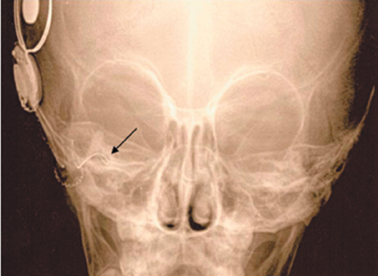

В результате удалось ввести 19 электродов из 22. Проведение интраоперационного тестирования имплантированного устройства – телеметрия нервного ответа (NRT) показала, что положительный ответ получен на 16 каналах электрода из 22. Послеоперационная трансорбитальная рентгенография улиток выявила, что активный электрод имплантата находится в общей полости (рис. 4). Таким образом, операция кохлеарной имплантации была успешно выполнена.